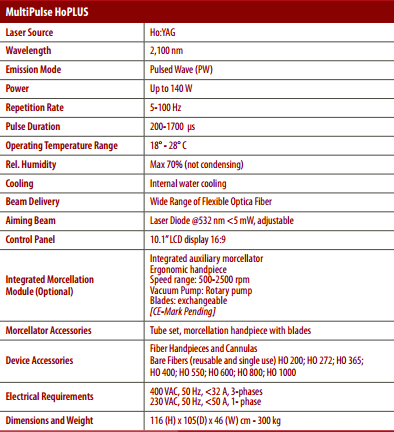

مشخصات فنی دستگاه